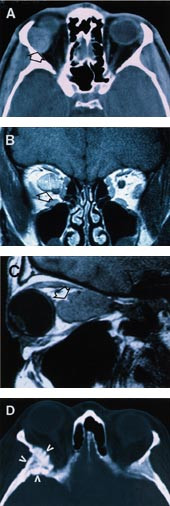

Innføring av CT og senere MR har hatt uvurderlig betydning for diagnostisering av orbitasvulster (fig 3). CT- eller MR-undersøkelse har vært utført hos 181 pasienter. Før vi fikk CT, var den mest benyttede teknikk ved vår avdeling orbitopneumotomografi, hvor luft ble injisert inn i Tenons kapsel og anvendt som kontrast (7). I alt 25 pasienter fikk påvist en svulst på denne måten. Den mest ”avanserte” undersøkelse utført hos de øvrige var cerebral angiografi hos fem og vanlig røntgenundersøkelse eller planigrafi av ansiktsskjelett, bihuler eller kranium hos 39. Det mangler opplysninger om utført røntgenundersøkelse hos 28 pasienter.

I materialet er 71 ulike svulsttyper representert, og noen eksempler er vist i figur 4. Tabell 3 – 7 gir en oversikt over ulike diagnoser med kjønns- og aldersfordeling. Dette inkluderer 177 benigne, 96 maligne og fem svulster med ukjent malignitetspotensial (pasientene ønsket ikke videre utredning). De hyppigst forekommende benigne svulster var mukocele, hemangiom, pseudotumor og meningeom. Av maligne svulster var non-Hodgkins lymfom vanligst. Blant metastasene var utgangspunktet oftest cancer prostatae eller cancer mammae. I tillegg har vi observert metastaser fra flere uvanlige kreftformer, deriblant paragangliom og malignt schwannom. Det var en overvekt av meningeom, sarkoidose og non-Hodgkins lymfom hos kvinner, mens pleomorft adenom var hyppigere hos menn. For de fleste svulsttypene er imidlertid antallet for lavt til at man kan angi noen sikker kjønnsspesifikk opphopning. Pasienter med optikusgliom, dermoid cyste og osteoid osteom hadde en lavere gjennomsnittsalder enn de øvrige. I tabell 8 presenteres en oversikt over orbitasvulster hos barn.